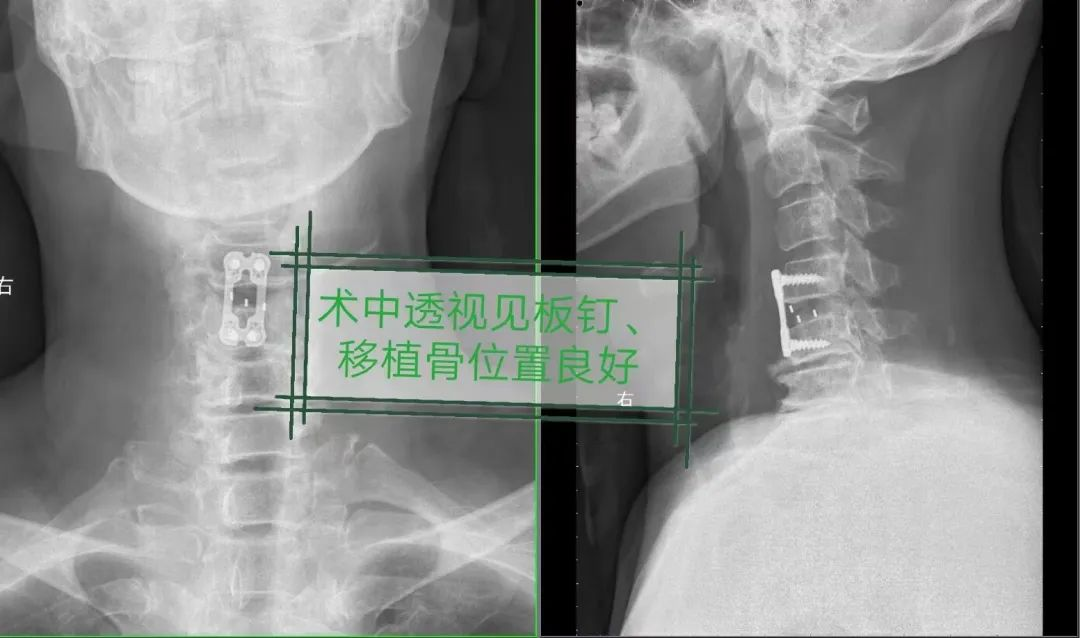

9月2日,鄭大爺患者送入手術室。經過3多小時的努力,張金鋒主任主刀,張朋主治醫師協助,帶領脊髓脊柱團隊完成頸椎間盤切除及椎管減壓,并實施頸椎融合和固定手術,通過頸部皮紋切口,逐層分開頸部肌肉的間隙,到達頸椎間盤的位置。在高倍顯微鏡下,使用微創磨鉆,顯微器械等切除突出的椎間盤和骨贅,解除脊髓和神經的卡壓,然后于椎間植骨融合內固定,重建頸椎的穩定性。

整個手術完全在顯微鏡下完成,手術區域可以放大到12倍,對壓迫脊髓的間盤和骨化后縱韌帶進行**減壓。在兩個椎體間的間盤操作空間很小,在狹小的空間操作,只有使用顯微鏡才可以做到對嬌嫩的脊髓很大的保護。